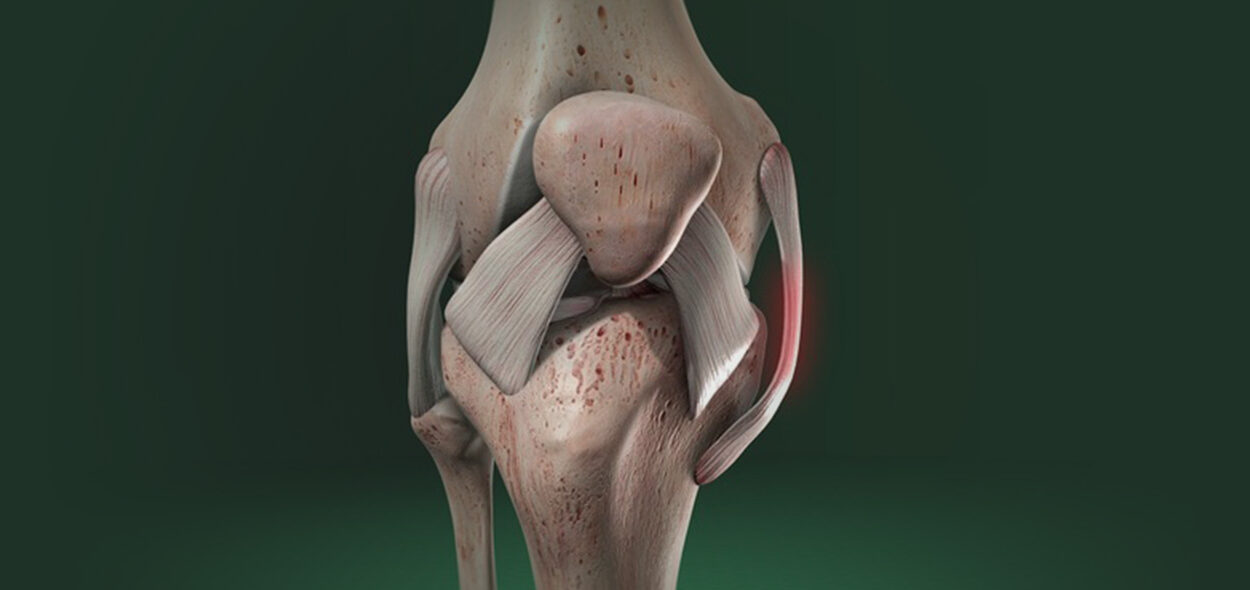

Dr. João Hollanda é médico ortopedista especialista em cirurgia do joelho com mais de 1.500 cirurgias de reconstrução do Ligamento Cruzado Anterior ao longo dos últimos 15 anos, incluindo atletas olímpicos de diferentes modalidades, atletas da Seleção Brasileira de Futebol e muitos “boleiros de fim de semana”.